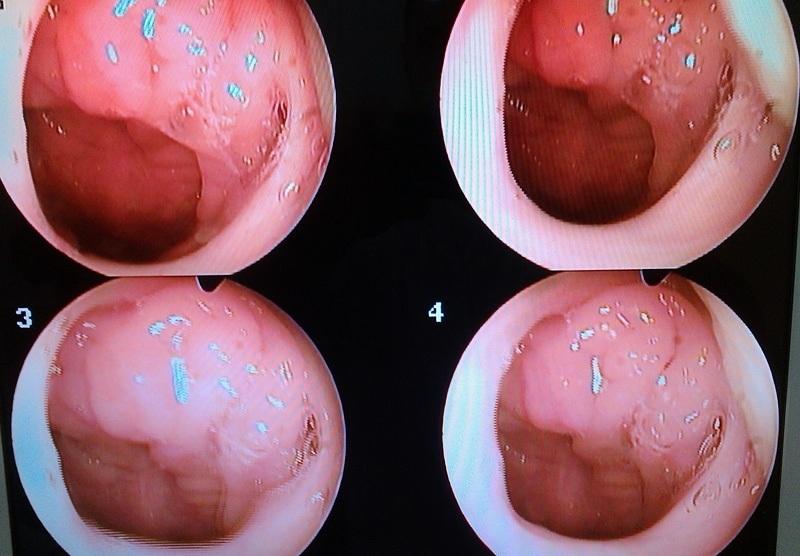

Аденоиды у детей представляют собой одну из наиболее распространённых проблем в возрасте от 2,5 до 6 лет. Эти аденоидные вегетации находятся на задней стенке носоглотки и напоминают по форме цветную капусту или красный петушиный гребень.

Если родителей интересует, как выглядят аденоиды в носу, то эту патологию можно подробно рассмотреть на фотографиях: